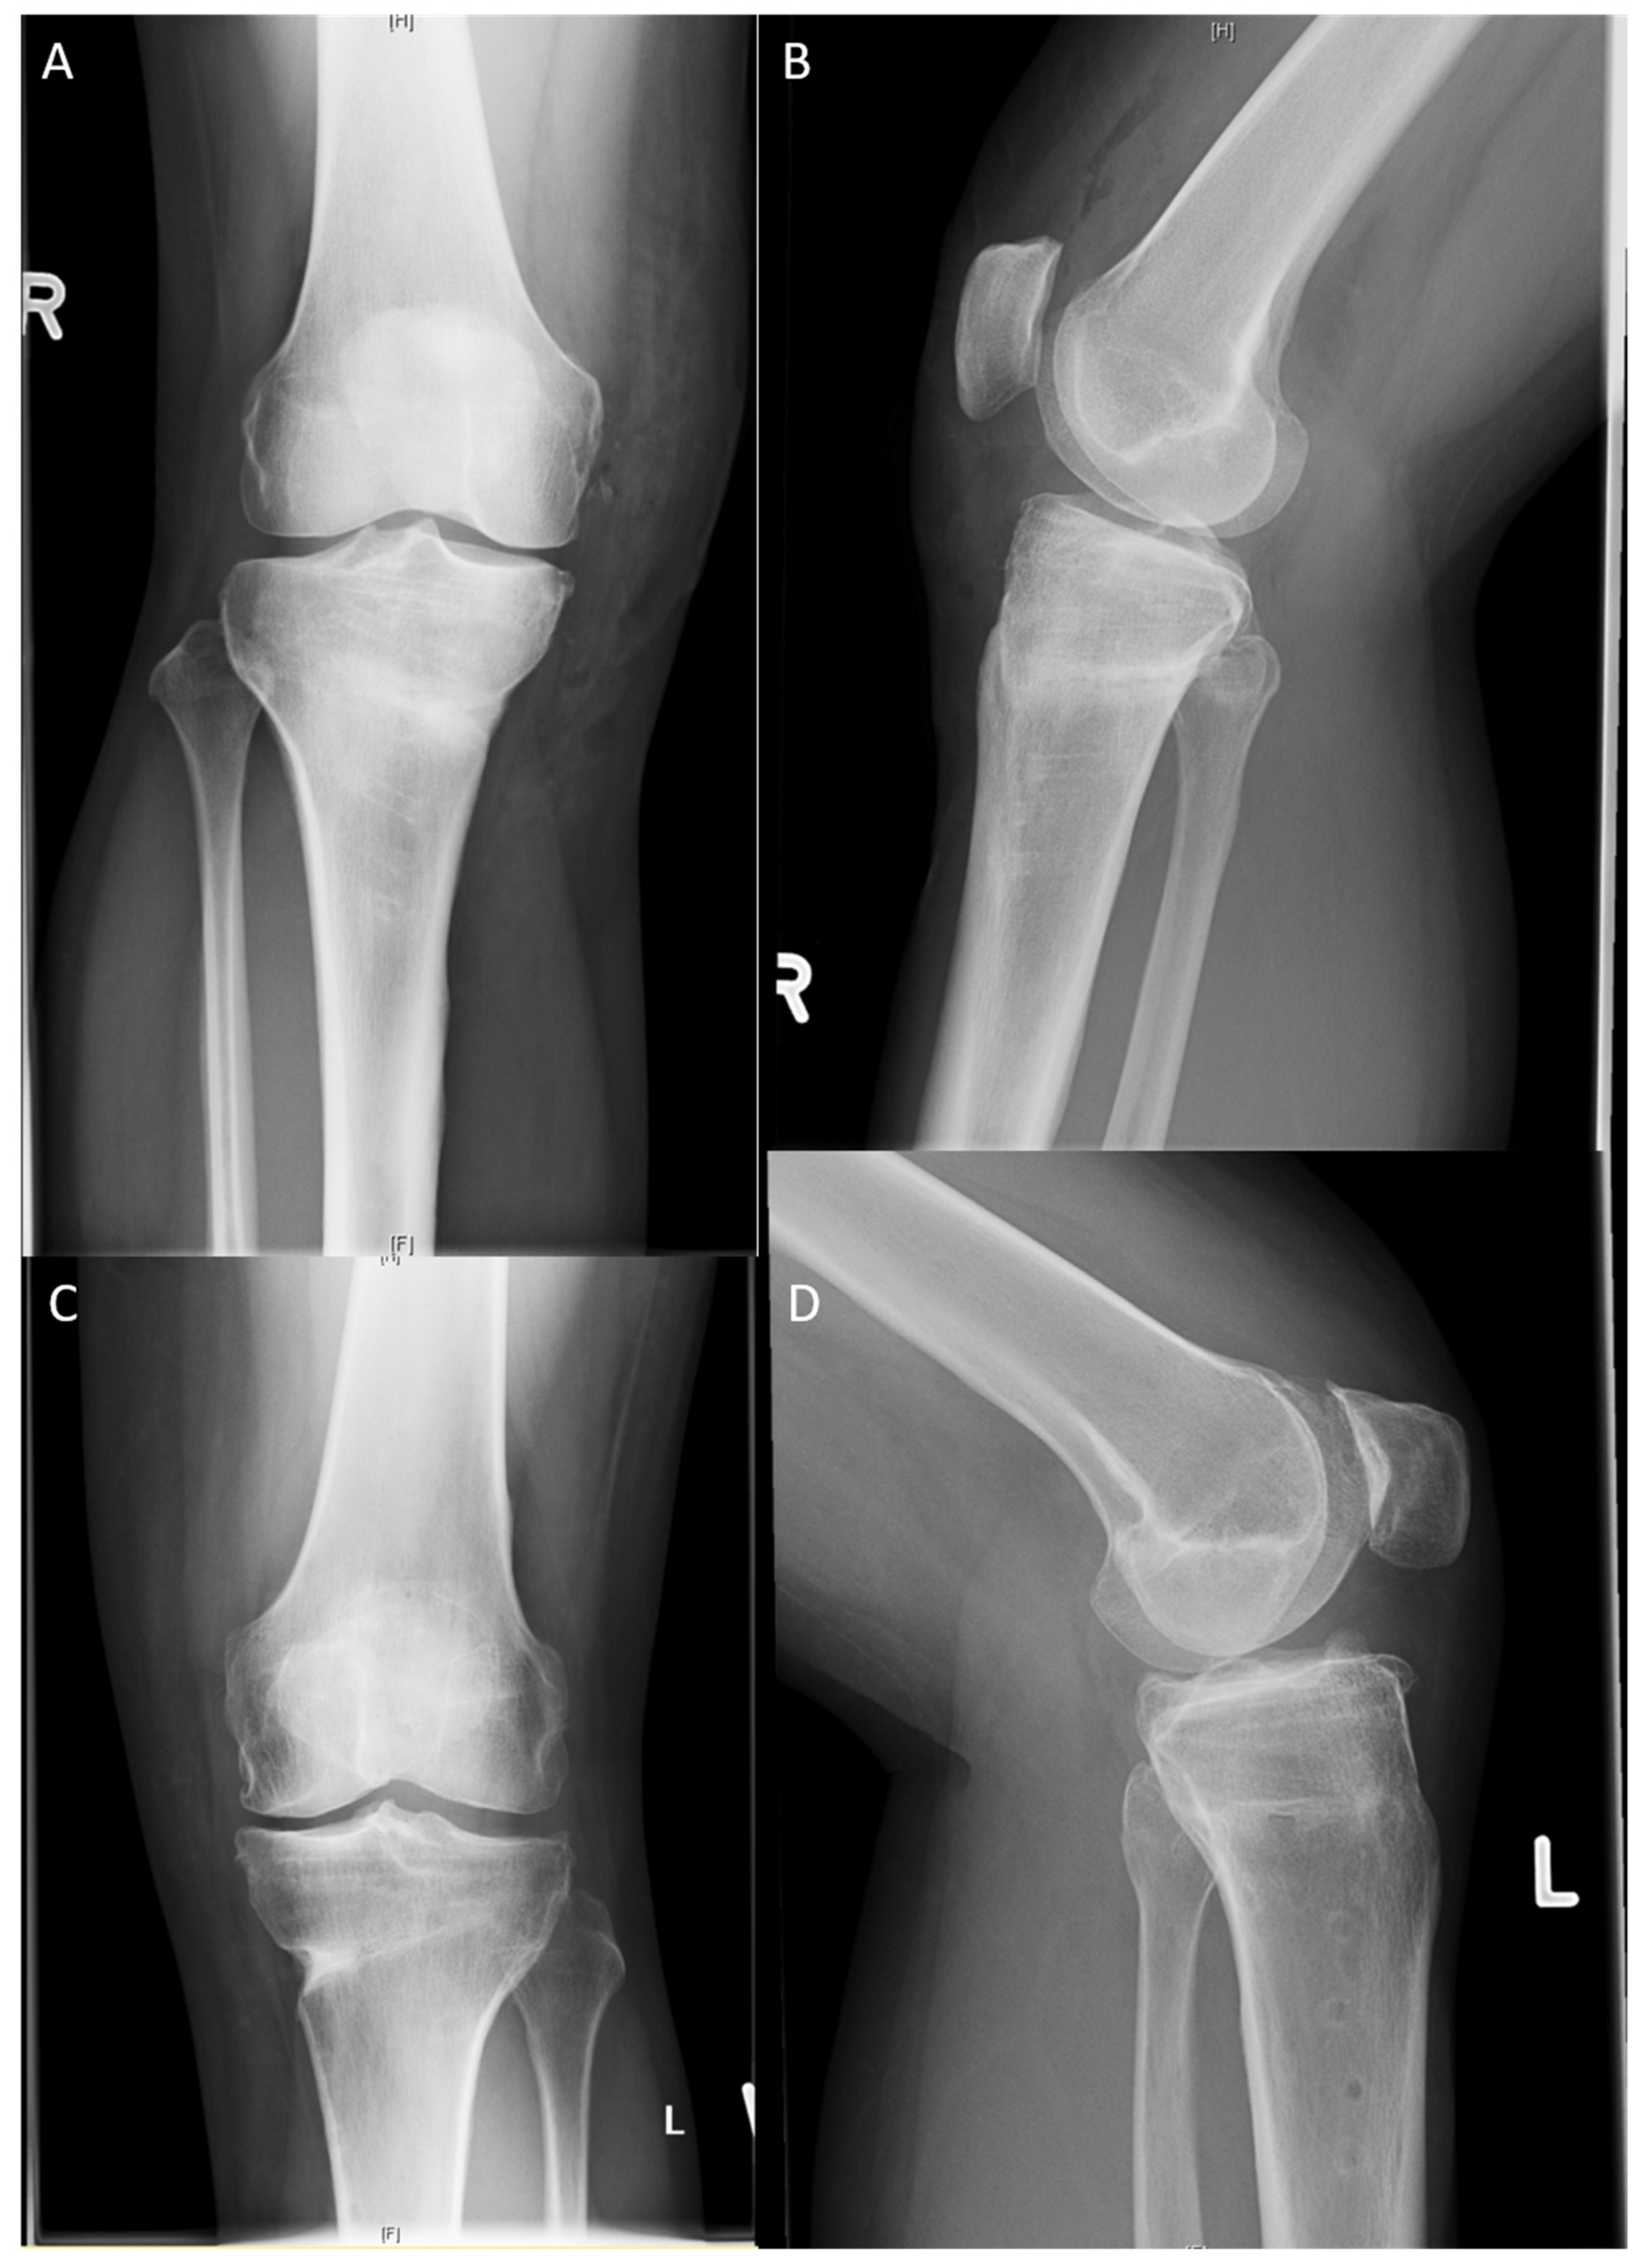

2.2. Surgical Technique